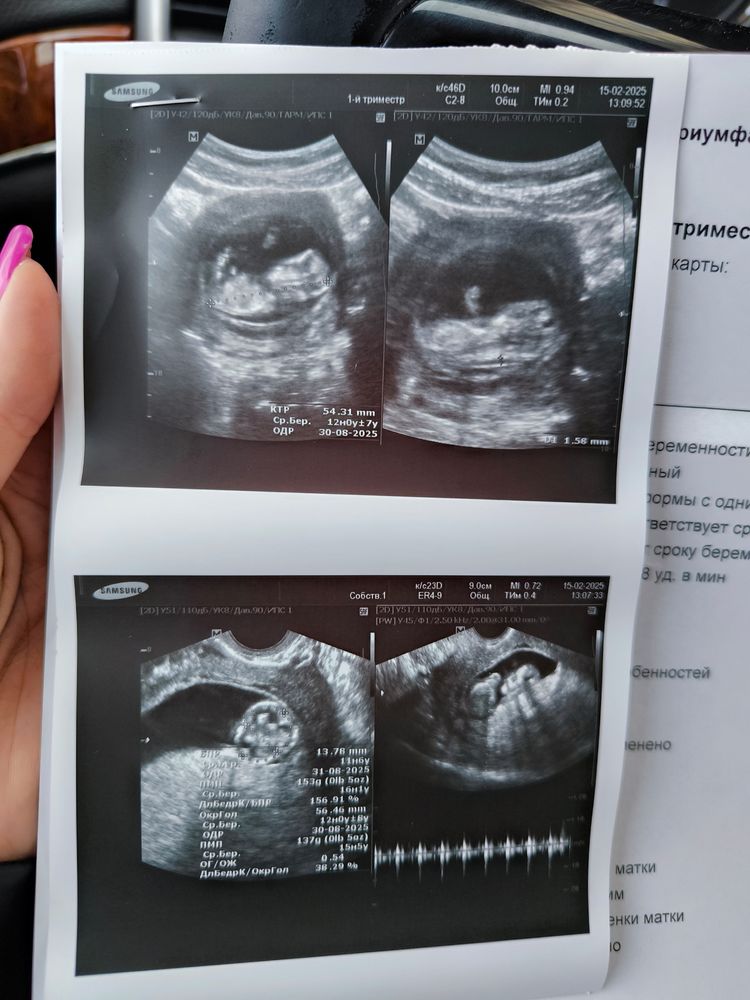

Скрининг 1 триместра!

Анализы, скринингиВ 11,2 прошла платный скрининг. По узи все хорошо: носовая кость 2,1, складка 1,8

Наталья, добрый день, проходида в платной клинике у врача, которому доверяю, мне важно было чтобы все показали, рассказали. В жк буду проходить в пятницу в срок 12,1 - меня врач записала в жк при постановке на учет сразу. Плод у меня опережает на 6 дней, все хорошо увидели